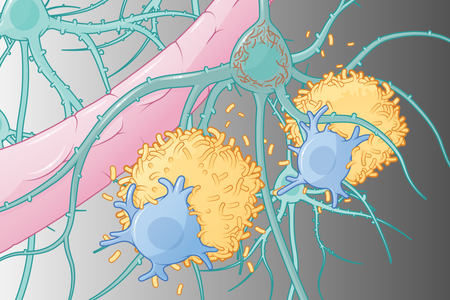

Alzheimer’s Drugs Are Finally Tackling the Disease Itself. Here’s How

While our understanding of Alzheimer’s disease is far from complete, the latest therapies, and others in more than 100 clinical trials, offer new hope